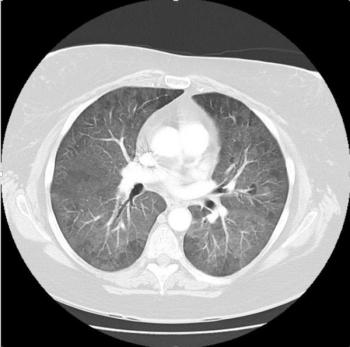

The mediastinal benign schwannomas is a nerve sheath tumor composed of Schwann cells. These tumors are often asymptomatic and found incidentally.

Two weeks after injury to the right chest wall and shoulder, the patient continues to have pain. He also reports numbness and tingling in his hands bilaterally. What do the ED images reveal?